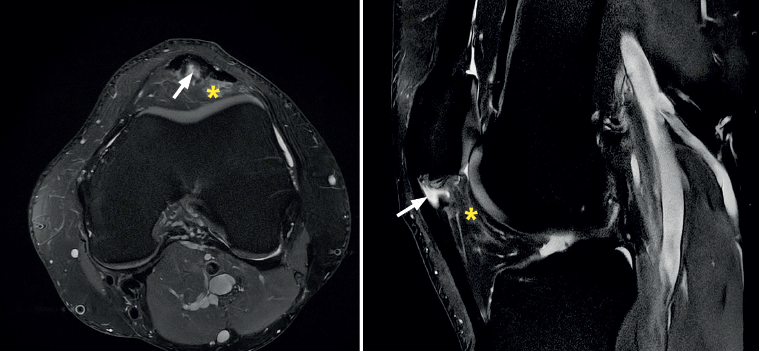

Magnetic resonance imaging diagnosis

The most common MRI finding is increased signal intensity in the lower pole of the patella, with local widening of the affected zone of the tendon (Figure 7)(14,25). The most evident advantage of MRI with respect to ultrasound is its capacity to visualise associated lesions in the joint and cartilage, as well as the presence of bone edema and involvement of Hoffa's fat pad (Figure 7). As clear disadvantages, mention must be made of the high cost of the technique and the impossibility of performing exploration in motion or at different angles of flexion of the knee.

Figure 7. Magnetic resonance imaging view showing alteration of the proximal patellar tendon with thickening and edema (white arrow), in a segment measuring 1.5 cm in length. Marked edema of adjacent Hoffa's fat pad (asterisk).